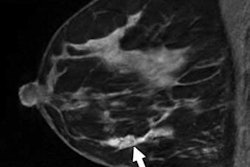

A team led by Dr. Cary Gross of Yale University's Cancer Outcomes, Public Policy and Effectiveness Research Center identified groups of surgeons who work with the same patients and determined which of them were using breast MRI to care for those with breast cancer. Gross' team investigated whether surgeons who did not initially use breast MRI -- but whose peers did -- were more likely to use the technology.

The researchers found that women whose surgeons were in peer groups with the highest breast MRI baseline use were more likely to undergo MRI exams than women whose surgeons' peers did not use MRI (24.9% compared to 10.1%).